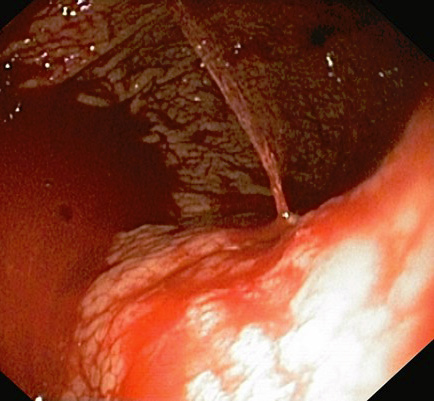

A 55-year-old male patient arrived at the Emergency Department of the Republican Vilnius University Hospital complaining of black stools and general weakness for only 1-day, tachycardia and low arterial blood pressure. UGIB was suspected. An extra esophagogastroduodenoscopy was performed. Arterial bleeding was observed from the posterior stomach wall in the border of the body/upper third of the stomach (Figures 1, 2). No pathological formations were visible in the mucosa. Dieulafoy’s lesion was suspected. The abdominal surgeon/endoscopist immediately started to stop the bleeding with adrenaline injection, but it was not enough. When we used endoscopic clip (Figures 3, 4). Bleeding was completely stopped. Patient’s condition was stabilized. But disease remained unknown. In order to reduce the risk of recurrent bleeding, we performed selective angiography of truncus coeliacus and embolization of the distal branches of arteria gastrica sinistra and some arteria lienalis branches, that feed formation through collateral blood flow (Figure 5). Large microspheres and pushing spirals were used for embolization (Figures 6, 7). The cause of bleeding still remained surely unknown. Now we suspected tumor. Only after by detailed strict anamnesis based on the patient’s life history, we conclude that the patient has a genetic disorder – Grönblad-Strandberg syndrome. According to our data, only four people suffer from this syndrome in Lithuania. Adjacent to this the patient had been operated for rectal cancer in the past, followed by ileostomy closure and abdominal wall hernioplasty for postoperative hernia. It is currently known that the patient has metastases in the liver and brain. The spread of cancer metastases, wide and severe comorbidities worsen the patient’s current condition, but despise these severe illnesses after proper and timely interventions, the patient lives without recurrent bleeding until now.

Figure 1. Bleeding site (endoscopic view)

Figure 2. Bleeding site (endoscopic view)